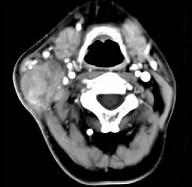

问题 65岁男性,吸烟史30余年,近半年来颈部出现疼痛性肿块,CT扫描如图所示,请选择最可能诊断()

选项 A.淋巴结核 B.血管瘤 C.神经鞘瘤 D.淋巴结转移瘤 E.软组织脓肿

答案 D